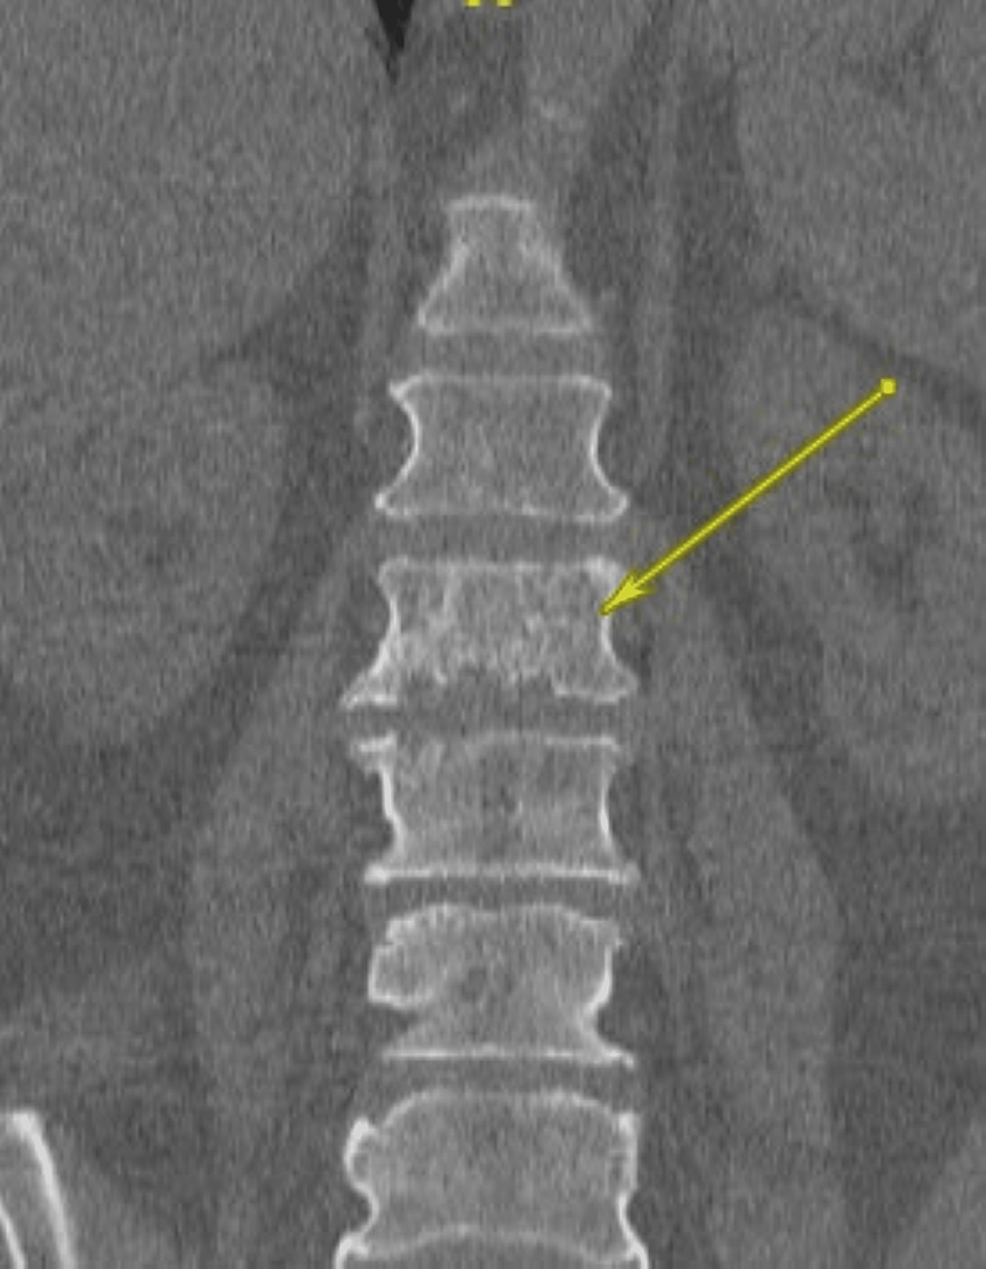

(a) CT Lumbar spine sagittal reformat revealing left L3L4 facet

(a) CT Lumbar spine sagittal reformat revealing left L3L4 facet Spinal Erosion Treatment you can look after your spinal discs by maintaining good posture and a healthy weight, practising safe lifting and doing. A spinal lesion describes any area of abnormal tissue on the spinal cord, whether it is benign (non. mri will show enlargement of the spinal canal with arachnoid diverticulae, erosion of the laminae and adherent nerve. you. Spinal Erosion Treatment.